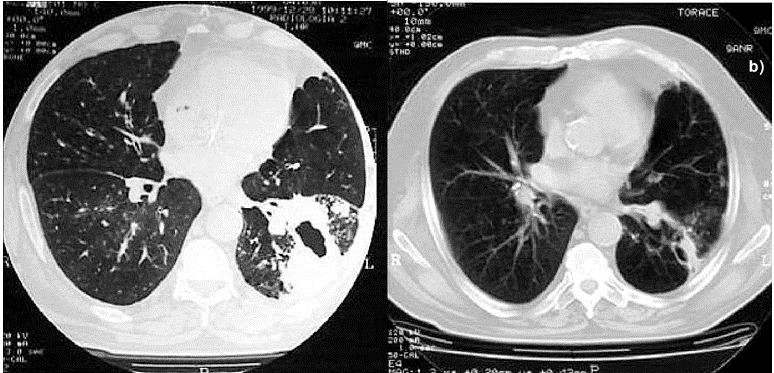

A lung window of a transverse thin-section CT scan (1.25-mm-section thickness) showing multiple cavities in both lungs. [Case of MDR-TB in a 29-year-old man]

Multidrug-Resistant Tuberculosis (MDR-TB) is a type of Drug-Resistant Tuberculosis (DR-TB) that is resistant to at least two of the most effective drugs used to treat TB, such as isoniazid, rifampicin and ethambutol. It is a serious public health concern since it is more challenging to treat and can spread more quickly than drug-sensitive TB.

Several factors, including improper treatment of TB, inadequate treatment regimens, and the emergence of M. tuberculosis strains with innate resistance to certain drugs, can cause MDR-TB. It can affect any part of the body, but it most commonly affects the lungs.

Symptoms of MDR-TB may be similar to those of drug-sensitive TB and may include a persistent cough lasting more than 3 weeks, chest pain, fatigue, weight loss, fever, and swelling of the neck (in case of lymph node involvement). However, the symptoms may be less severe because the bacteria grow more slowly.

HRCT of a patient before and after including levofloxacin, showed improvement of the cavitary lesion in the apical segment of the lower lobe after 15 months

WHO suggests the use of the 6-month treatment regimen composed of bedaquiline, pretomanid, linezolid, and moxifloxacin (BPaLM) rather than 9-month or longer (18-month) regimens in MDR-TB patients. Patients should be included with levofloxacin, moxifloxacin, and linezolid on longer regimens.

Bedaquiline should be included in longer multidrug-resistant TB regimens for patients aged 18 years or more. For patients on longer regimens, a treatment duration of 15–17 months after culture conversion is suggested for most patients; the duration is modified according to the patient’s response to therapy.